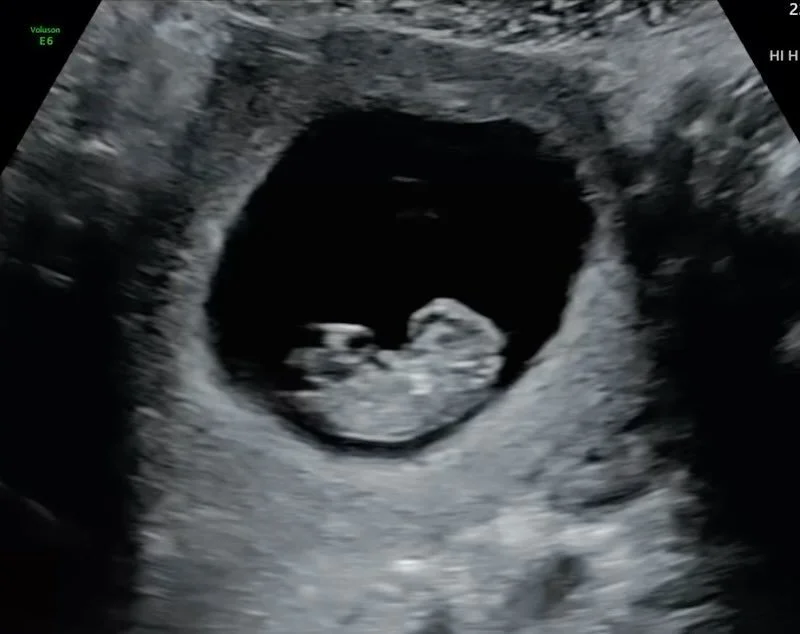

Welcome to Sentiments 4D Ultrasound Studio where beautiful memories begin. Our studio offers a warm, relaxing environment designed to make every visit special and stress-free. With over 10 years of professional ultrasound experience, you can trust that you’re in skilled and caring hands. From early heartbeat scans to breathtaking 3D/4D/HD live imaging, we’re here to help you connect with your baby in the most meaningful way.

In addition to elective ultrasounds, Sentiments offers comprehensive diagnostic obstetric and gynecologic imaging. Our scans are performed with precision, compassion, and attention to detail β€” ensuring you receive accurate results in a comfortable, stress-free environment.